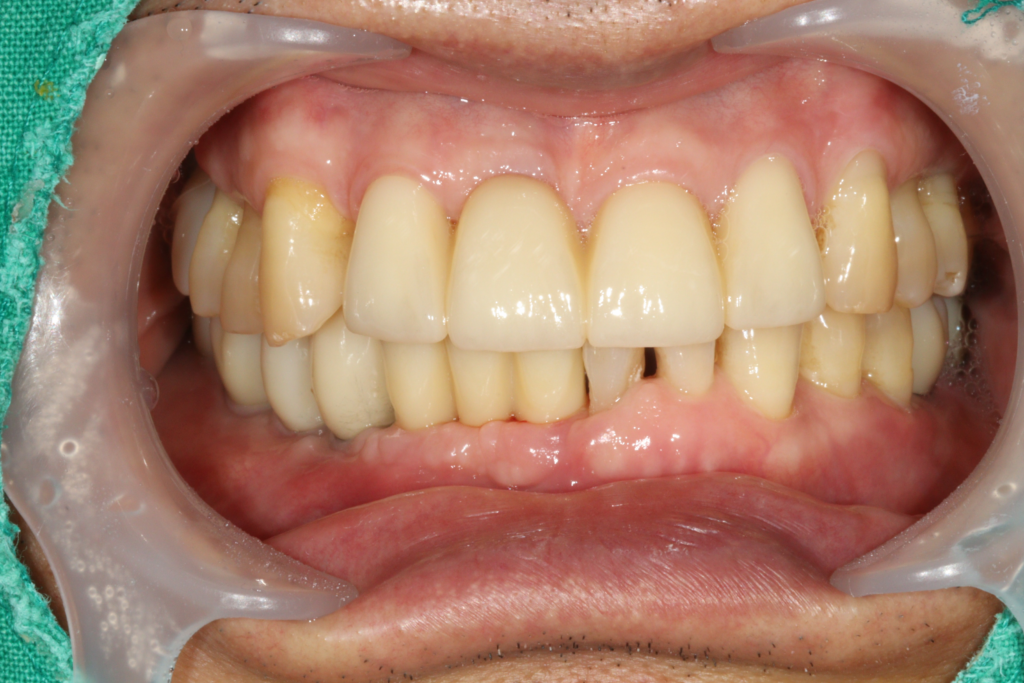

시술 후

26.10.07

26.01.07

치아 발치가 필요하다는 이야기를 들으면 많은 분들이 걱정을 하시지만, 최근에는 발치 후 임플란트 식립을 통해 치료 기간을 줄이고 자연스러운 결과를 얻을 수 있는 방법도 다양하게 시행되고 있습니다. 다만 모든 환자에게 즉시 식립이 가능한 것은 아니기 때문에 정밀 검사와 충분한 상담을 통해 개인에게 맞는 치료 계획을 세우는 과정이 중요합니다.